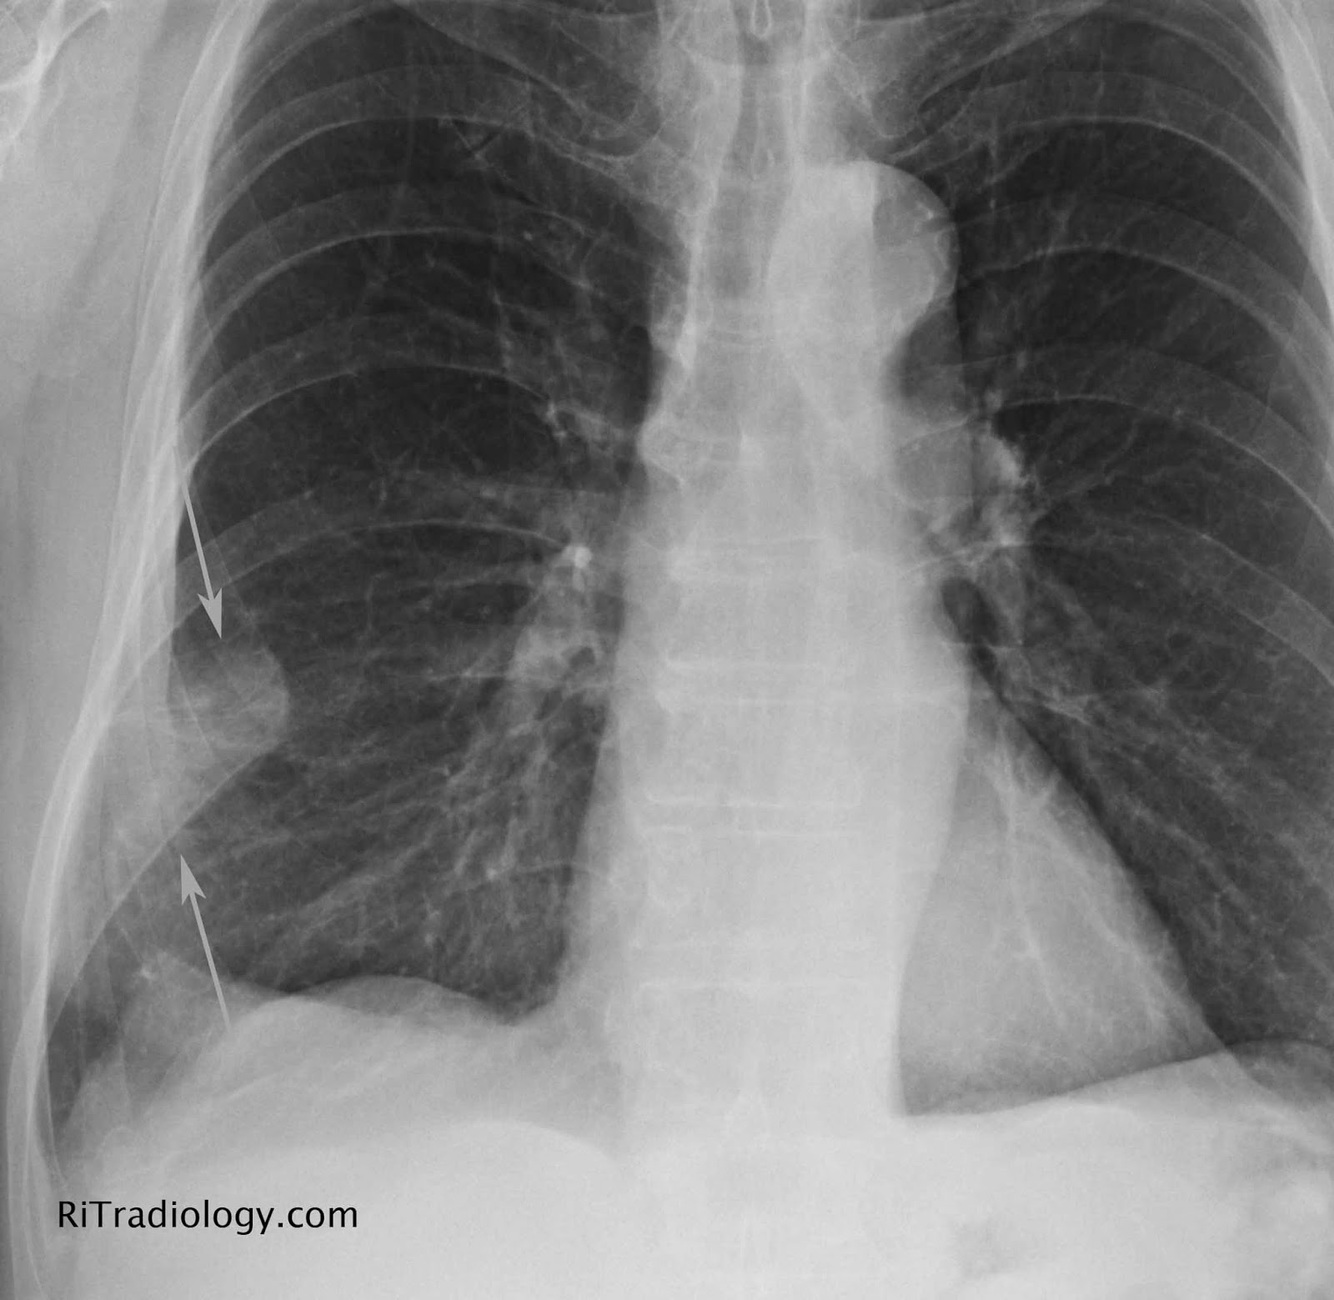

Qual o nome deste sinal?

O que significa?

Sinal de HAMPTON

Área de hipotransparência em cunha - local do infarto pulmonar - TEP

Sinal de PALLA

Dilatação do ramo descendente da artéria pulmonar